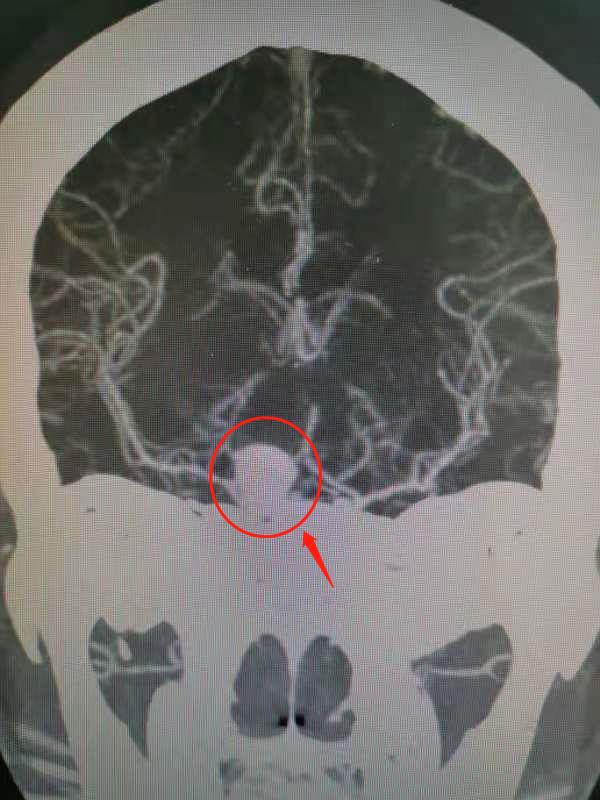

通讯员(彭思民)近日,新昌县人民医院神经外科成功救治一名右侧颈内动脉床突段巨大动脉瘤(颅内)破裂出血患者,这是人民医院首次完成高难度颅内巨大动脉瘤手术治疗。 石女士今年40岁,于6月10日凌晨1点半左右,因“头痛剧烈、恶..